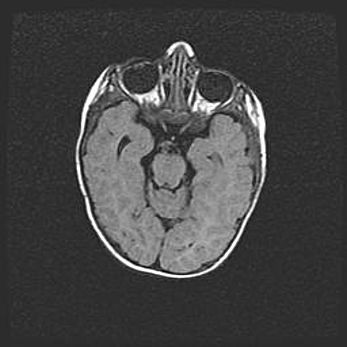

Наружная гидроцефалия с возможной атрофией височных областей.

Возраст: 28 дней

Вес: 3670 г

Пол: мужской

Окружность головы: 38 см

Срок гестации: 40 недель

Гидроцефалия головного мозга у новорожденных – это заболевание, которое характеризуется скоплением избыточного количества спинномозговой жидкости в желудочковой системе головного мозга в результате затруднения её перемещения от места выработки к месту поглощения в кровеносную систему или вследствие нарушения абсорбции. При открытой наружной форме гидроцефалии у новорожденных расширяются и переполняются субарахноидные пространства.

При нормотензивных  формах,  которые,  как  правило,  являются  следствием  перенесенных ишемических  повреждений  паренхимы  мозга,  возможно  сочетание микроцефалии  с нормотензивной гидроцефалией. В основе данных изменений лежит атрофия больших полушарий с преимущественной  локализацией  в  лобно-височных  областях.